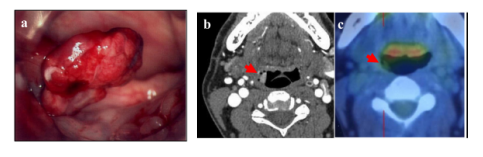

2006.9 HCC首次转移咽部:患者就诊,主诉吞咽不适。医生在该患者的下咽发现带蒂息肉,活检结果提示HCC转移。后续的颈椎部CT以及PET-CT显示带蒂息肉位于会厌右侧。

图4.从左到右分别为:带蒂息肉转移灶肉眼观察;CT结果;PET-CT结果

2006.10 患者进行了咽部息肉切除术。免疫组化染色发现肿瘤细胞的肝细胞特异性抗原(Hep Par-1)染色阳性,考虑为HCC转移。随后患者被给予口服替加氟(FT)/吉美嘧啶(CDHP)/奥替拉西(Oxo)进行治疗。